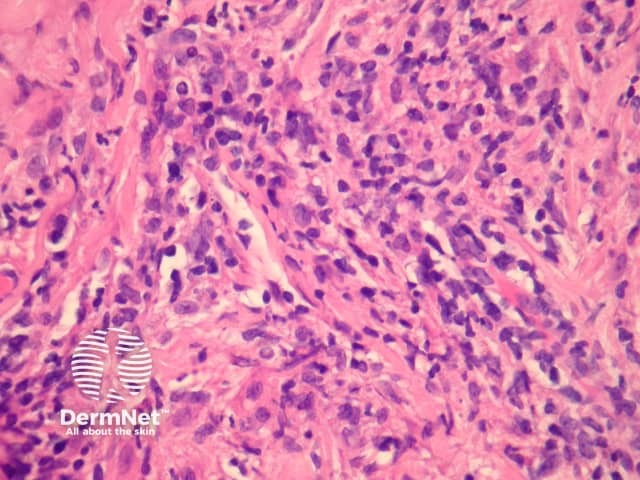

In extranodal NK/T cell lymphoma, nasal type, there is a dense dermal infiltrate (figure 1) which often extends into the subcutis. Exocytosis of atypical lymphocytes into the epidermis may be seen and may closely resemble mycosis fungoides (figure 2). The infiltrate in the dermis is usually polymorphous and may include numerous histiocytes and eosinophils. The atypical cells are small to medium sized with some larger forms (figures 3, 4). Commonly, the infiltrate infiltrates the walls of vessels (figures 3, 4) causing vascular nuclear debris (seen focally in figure 4). Necrosis is another common finding.

Figure 4